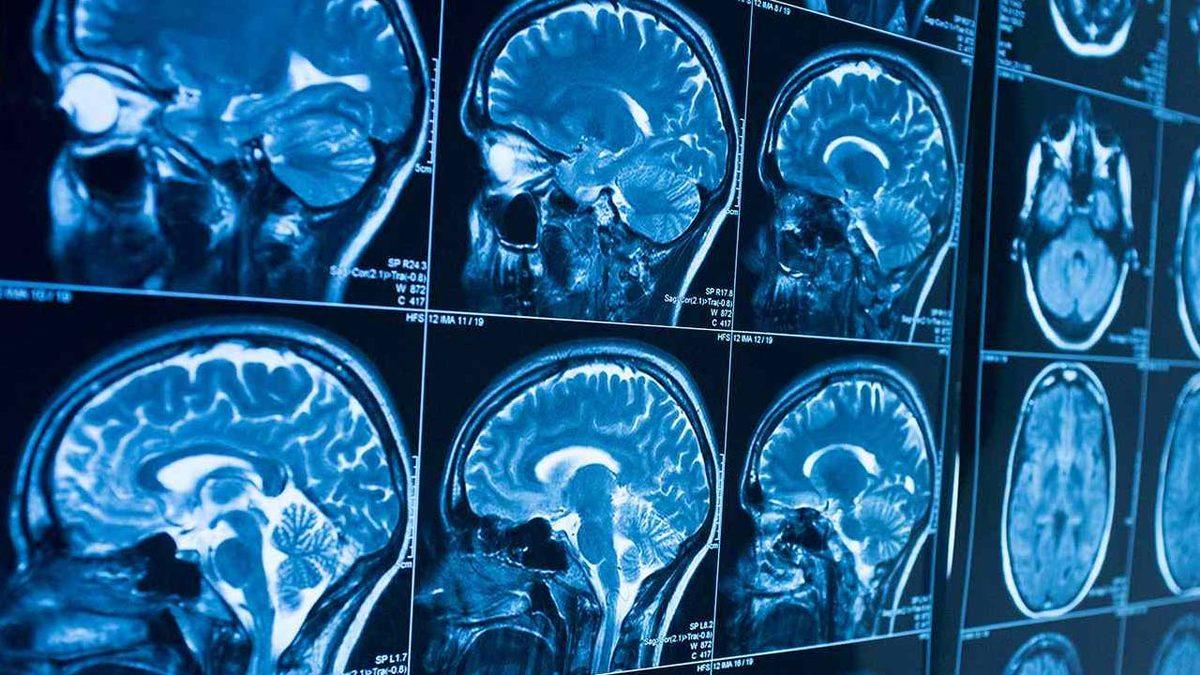

Avustralya’daki tıbbi araştırma laboratuvarı Australian Sports Brain Bank, tarihte ilk kez bir kadın sporcuda “kronik travmatik ensefalopati (KTE)” tespit edildiğini açıkladı. KTE, kafaya alınan birden çok kuvvetli darbeyle oluşuyor, beyindeki sinir hücrelerinin zamanla giderek daha fazla azalmasına yol açıyor.

KTE tanısı, ancak ve ancak kişinin ölümünden sonra beyninde yapılan otopsi sonucunda konulabiliyor. Tarihte KTE tanısı konulan ilk kadın sporcu, kasım ayında hayatını kaybeden 28 yaşındaki Avustralya futbolu oyuncusu Heather Anderson oldu.